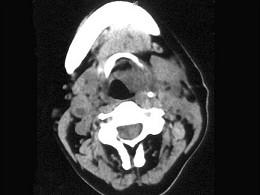

女,54岁,鼻咽部异物感约3个月,PE:左侧声带固定,可见肿物,CT如图所示,应诊断为 ( )

鼻咽癌( )